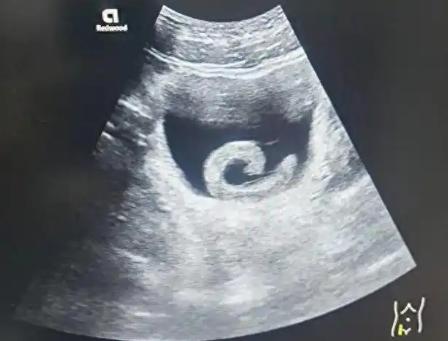

太离谱了!河南郑州,一男子听信“偏方”,将5厘米的水蛭塞进尿道,水蛭顺着尿道向内爬行“安家”膀胱,开始疯狂吸血释放抗凝血物质。 河南郑州23岁的郑勇(化名)在刷短视频时,无意间刷到了一条声称有 “特殊功效” 的偏方视频。 视频里模糊地提到,活体水蛭能通过某种 “自然疗法” 改善身体状态,配上一些似是而非的案例和夸张的效果描述,让对新鲜事物充满好奇的郑勇动了心。 年轻人总容易被这种小众又离奇的说法吸引,加上视频里说这种方法 “安全无副作用”,郑勇没多想,就通过视频里的链接网购了一条活体水蛭。 收到快递时,那条 5 厘米长的黑棕色水蛭还在密封袋里不断蠕动,吸盘一张一合,看着就让人头皮发麻,但猎奇心已经压过了恐惧,郑勇还是决定按照偏方说的做。 他找了个没人的房间,照着视频里的方法,硬着头皮将水蛭往自己的尿道里塞。起初只感觉到轻微的异物感,水蛭体表的黏液让它滑动起来并不费力,可就在完全塞入的瞬间,一阵尖锐的刺痛突然传来。 郑勇本以为是暂时的不适,想着忍一忍就能等到 “奇效”,可疼痛不仅没消失,反而越来越剧烈,像有无数根细针在尿道里来回穿刺。 更让他崩溃的是,原本正常的排尿变得异常困难,每一次尝试都伴随着灼烧般的剧痛,尿液里还混着暗红的血丝。 他不知道的是,这条被塞进尿道的水蛭,并没有停留在原地,凭借着三千万年进化出的生存本能,水蛭能将身体压缩到原本的五分之一大小,轻松穿过直径仅 5 到 7 毫米的尿道管道。 它前端的吸盘带着每平方毫米 200 个刀片状的微型锯齿,一边切割着脆弱的尿道黏膜,一边分泌着天然麻醉剂,让部分痛感暂时被掩盖,而自己则顺着湿润的尿道一路向内爬行。 大概过了三个多小时,郑勇的下腹部开始出现持续性的胀痛,就像揣了个充满水的气球,连走路都直不起腰。 这时候他脸色苍白得像纸一样,浑身冒冷汗,头晕眼花的,连站都站不稳,最后实在扛不住,才让朋友赶紧送他去了郑州市人民医院的泌尿外科。 接诊的医生听完郑勇吞吞吐吐的讲述,当场就愣住了,医生接诊过不少尿道异物的患者,有往里面塞磁力珠的,有塞体温计的,甚至还有塞细电线的,但往尿道里塞活体水蛭的,这还是头一例。 他赶紧安排郑勇做紧急检查,通过膀胱镜一看,那条5厘米长的水蛭已经爬到了膀胱里,身体因为吸饱了血,比原来膨胀了一圈,牢牢地吸附在膀胱壁上,周围的膀胱黏膜已经被刺激得红肿糜烂,还有好几处渗血点。 李医生当时就严肃地跟郑勇说,万幸送医还算及时。 要知道,水蛭在吸血的时候,会释放出大量的水蛭素,这种物质的抗凝效果是临床常用抗凝药肝素的5到10倍,能牢牢锁住体内的凝血酶,让伤口一直渗血。 要是再晚来几天,不仅可能因为持续出血导致严重贫血,还可能引发膀胱穿孔、尿脓毒血症,这些并发症要是控制不住,随时会危及生命。 医院立刻安排了紧急手术,由泌尿外科副主任医师带队,实施经尿道膀胱异物取出术。 这种手术是微创手术,不用开刀,医生通过尿道通道,把带有微型摄像机的内窥镜伸到膀胱里,在高清视野下精准找到水蛭的位置。 不过取水蛭的时候特别小心,因为水蛭的吸盘吸附力极强,要是强行拉扯,很容易把虫体扯破,残留的组织会引发更严重的感染和过敏反应。 医生耐心等了几分钟,趁着郑勇呼吸平稳、膀胱肌肉放松的间隙,迅速用异物钳夹住水蛭的中部,稳稳地把它完整取了出来。 医生表示像郑勇这样的尿道异物患者,科室每年都会接诊数例,异物种类五花八门,但活体生物的危害尤为严重。 水蛭这类生物不仅会吸血,还可能携带嗜水气单胞菌等病原体,通过伤口进入人体引发感染。 而尿道作为人体重要的排泄通道,一旦被异物侵入,很容易造成机械损伤,引发尿频、尿急、血尿等症状,严重时还会导致尿道狭窄、反复感染,甚至影响终身的排尿功能。 医生特别提醒,网络上流传的各种偏方大多没有科学依据,尤其是涉及到侵入人体的方法,风险极高。 人体不是试验场,任何违背常识的猎奇行为都可能付出惨痛的代价。 年轻人在面对网络上的新奇说法时,一定要保持理性判断,不要被猎奇心理冲昏头脑,遇到健康问题应该通过正规渠道咨询医生,而不是轻信没有科学依据的偏方。 对于这件事,您有什么想说的吗?欢迎评论区留言讨论。 信源:长城网2026-01-06——《23岁男子信偏方把5cm水蛭塞进尿道致剧烈疼痛、排尿困难,就医后通过手术取出异物,医生提醒》